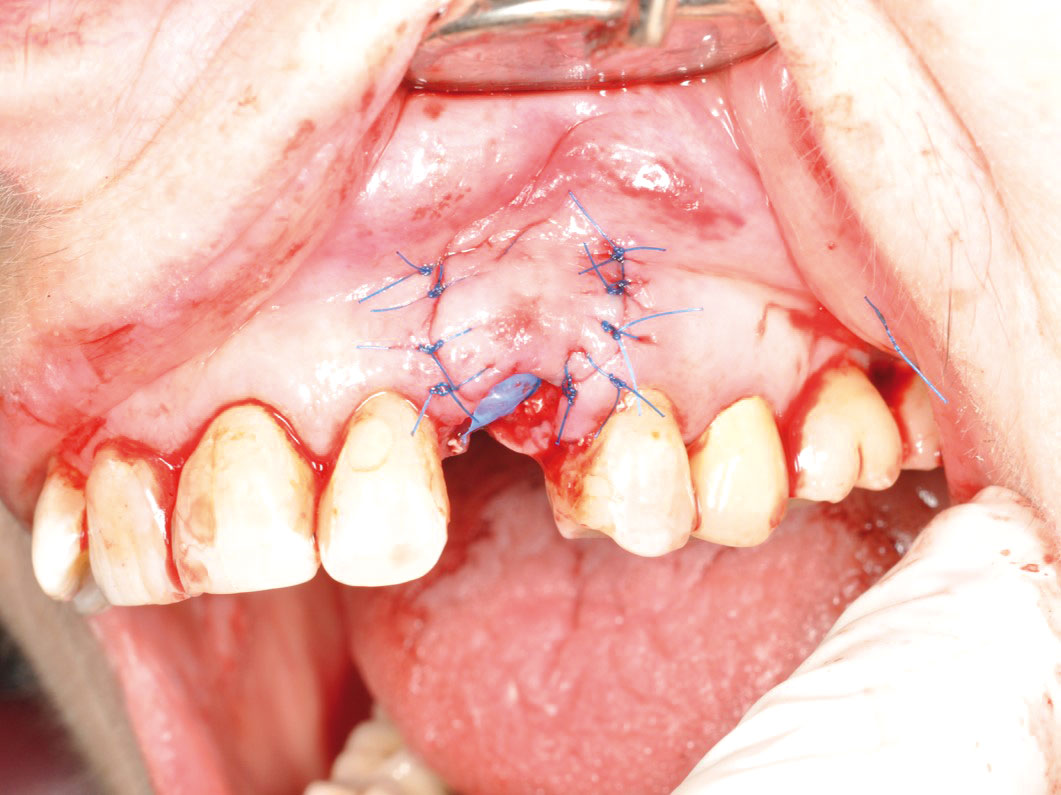

GBR and soft tissue augmentation with cerabone® and mucoderm® - H. Maghaireh & V. Ivancheva

Initial situation: missing teeth #11 & 12 and badly broken #21 root